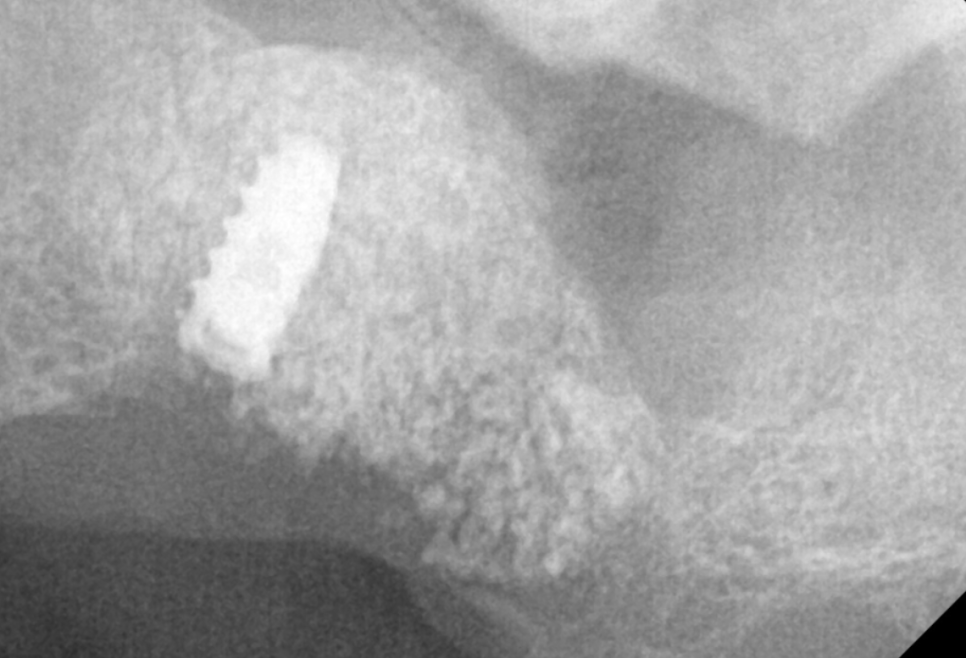

특히나 상악 치아

윗니는 상악동 염증으로 인해

잇몸뼈가 많이 없었는데요.